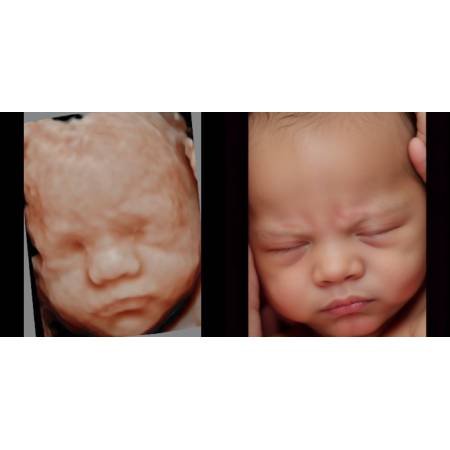

¿En qué consisten las imágenes 8K (Ultrasonido 8K)?

Es un programa que a través de inteligencia artificial (IA) perfeccionan y corrigen las imágenes para lograr una foto más realista del rostro fetal.